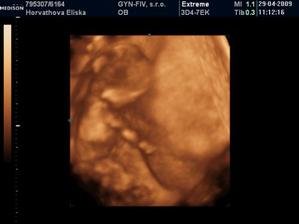

Dvojicky po KET

tak sme sa dockali-nase dvojicky sa narodili v 37+1 tt -20.10.09 cisarskym rezom -11:00 Matúško 3150g a 48cm a 11:02 Natálka 3030g 48cm,